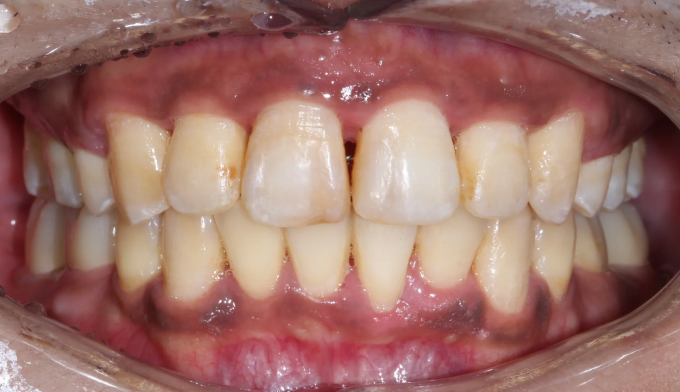

뻐드러진 앞니로 인한 돌출입과, 구강위생관리 부족으로 인한 다수의 충치가 관찰된 케이스입니다.

교정치료는 24개월 소요되었으며, 뻐드러진 앞니로 인해 다물기 어려웠던 입술도 이제는 편하게 다물 수 있게 되었습니다.